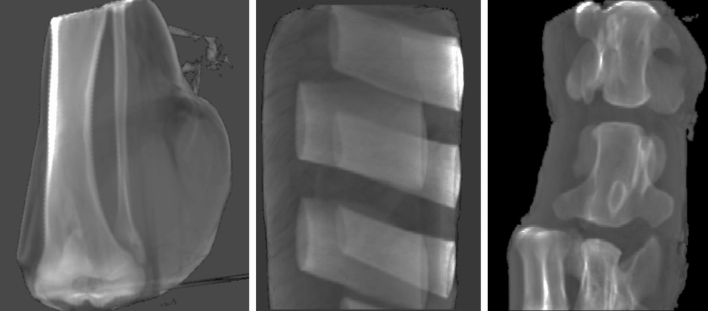

Bone tissue analyzed in this work were the tibial and fibular head and shaft from the porcine knuckle, bovine vertebrae from the oxtail, and rib bone from the bovine rib cut. Soft and adipose tissues were segmented from all samples. Figure 6 shows renderings of the specimen used.

Figure 6.

Renderings of porcine and bovine tissue samples applying summed voxel projection. From left to right: porcine knuckle (leg), bovine rib cut, and bovine vertebrae in oxtail sample.